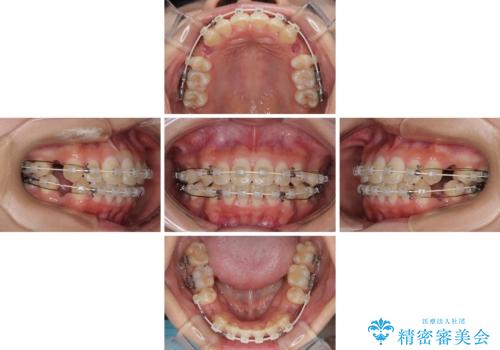

- 前歯のデコボコと唇の閉じにくさを気にして来院された患者様です。

単純に上下左右の第一小臼歯4本を抜歯して口元の突出感を改善することも考えられましたが、上顎骨よりも下顎骨の幅が広いため、より良い咬み合わせを達成することを目的として、急速拡大装置を用いて上顎骨を拡大することとしました。

歯列矯正では基本的に骨格を改善することはできませんが、急速拡大装置(MARPE)を使用することで上顎骨を側方に拡大させることができ、咬合状態を大きく改善することができます。